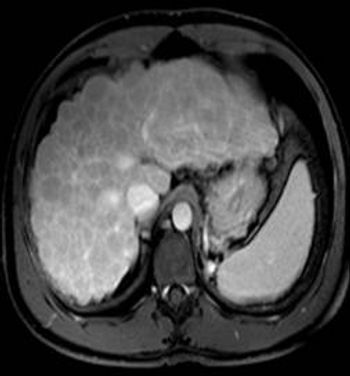

Case History: 60-year-old female with right hypochondriac pain, asthenia and decreased appetite.